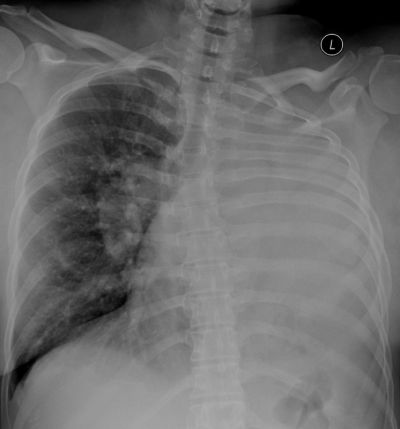

女性,38岁主诉:呼吸困难38年,加重伴全身水肿一周 看

女性,38岁主诉:呼吸困难38年,加重伴全身水肿一周 看看是什么情况?